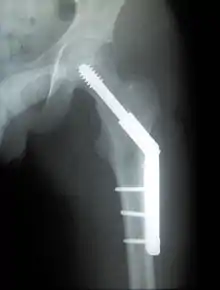

كسر عنق عظمة الفخذ

في الكسور ذات الدرجة المنخفضة (أنواع جاردن 1 و 2)، العلاج الأساسي هو تثبيت الكسر في موقعه بمسامير أو بشريحه ومسامير منزلقه. هذا العلاج يمكن أيضا أن يعالج الكسور المتحركه من مكانها بعد أن يتم اعادتها إلى وضعها الصحيح.

في المرضى المسنين مع الكسور المتحركه من مكانها الكثير من الجراحين يفضلون إجراء Hemiarthroplasty {تغير نصفي للمفصل}، تغييرالجزء المكسور من العظمة بأجزاء معدنيه. ميزة هذه العملية أن المريض يمكن أن يتحرك دون الحاجة لانتظار التحام العظم.

كسر ما بين النتوئين

وكسر ما بين النتوئين، تحت عنق عظم الفخذ، لديه فرصة جيدة للشفاء. العلاج يشمل تثبيت الكسر عن طريق شريحه ومسمار لتثبيت طرفين الكسر في مكانهما. يتم ادخال مسمار كبير في رأس الفخذ عبر الكسر، وتمتد الشريحه للأسفل على جسم عظمة الفخذ، مع وضع مسامير صغيرة لتثبيتها في المكان.